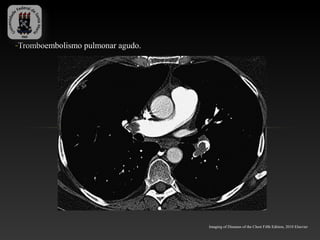

-Tromboembolismo pulmonar agudo.

Imaging of Diseases of the Chest Fifth Edition, 2010 Elsevier